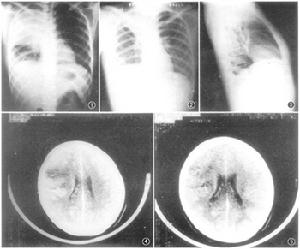

首次系统揭示人感染H7N9禽流感病毒临床特征,发现71.2%的患者发病一周内出现呼吸窘迫综合征、肺组织实变等并发症,发现延迟抗病毒治疗及伴有基础疾病是重症和死亡的危险因素,为临床救治提供了关键依据。新英格兰头条刊登该研究成果。

国际上一直缺乏“细胞因子风暴”治疗的有效手段,我们创造性将李氏人工肝用于重症H7N9救治,发现能有效消除“细胞因子风暴”,显著降低病死率,创建了呼吸衰竭救治新技术,人工肝治疗适应证首次发表于新英格兰。